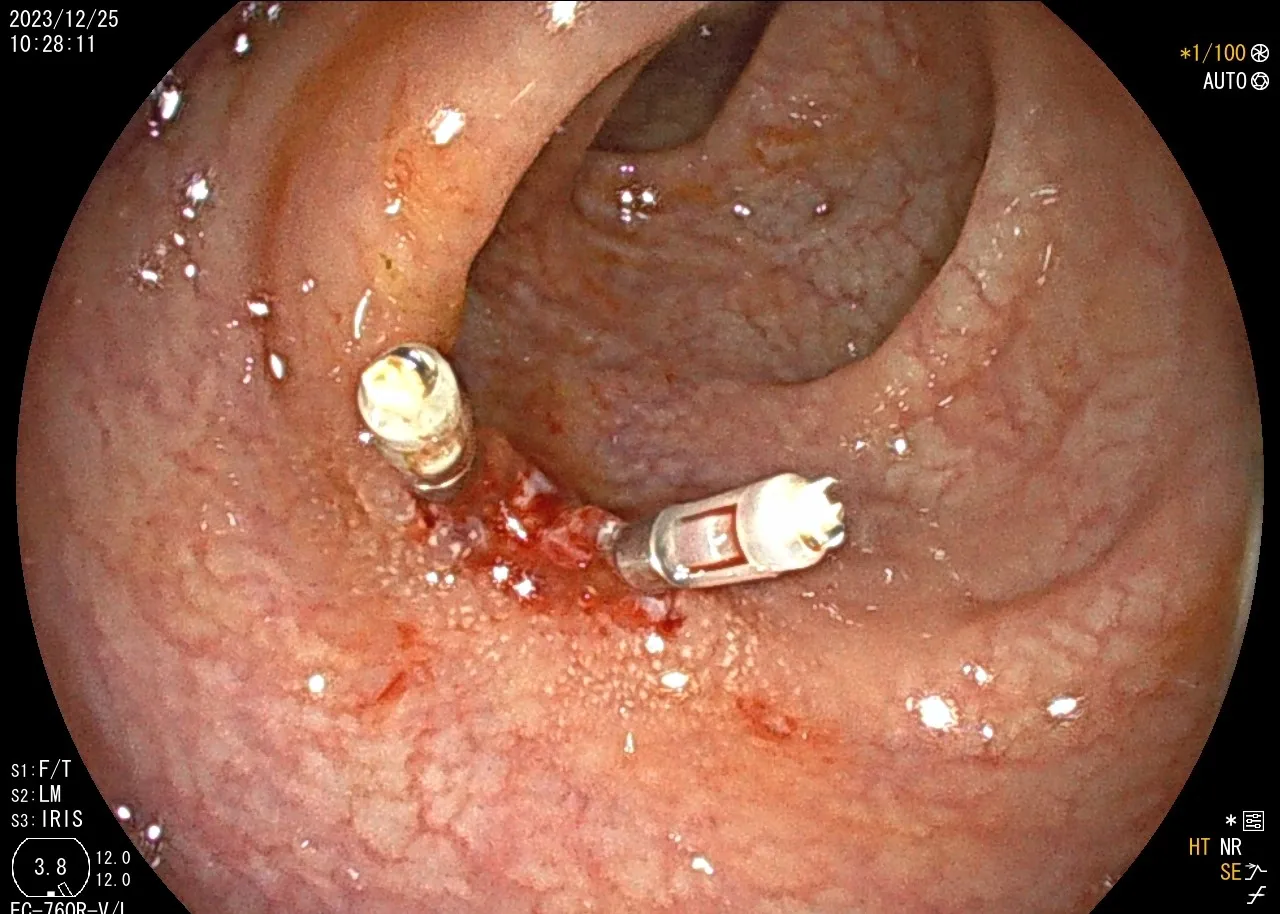

年前,一位40歲無任何病史的吳小姐來院接受全套健檢,於無痛大腸鏡的檢查中,在乙狀結腸意外發現一顆約1.5公分的息肉,當下使用BLI 觀察息肉型態,認為是NICE分類第二型(腺瘤),當下執行息肉切除術將整顆息肉完整切下並送化驗,結果病理報告診斷為大腸癌;

🏩後續協助患者轉診台北馬偕醫院直腸外科醫療團隊做後續大腸癌期別確認與近一步手術治療。術後證實大腸癌已完整切除。無需再作進一步化療或放療。🌡️